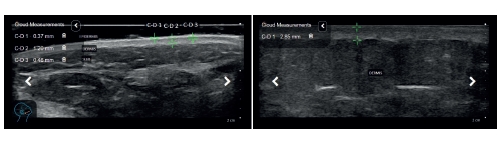

Por otro lado, la banda subepidérmica de baja ecogenicidad (SLEB) es un indicador clave en estudios de ultrasonido dermatológico. Esta banda, visible mediante el Scanner Clarius PAL HD, muestra alteraciones en la piel relacionadas con el envejecimiento y el estrés oxidativo. Un engrosamiento de la SLEB puede indicar inflamación y daño dérmico, mientras que su adelgazamiento sugiere pérdida de colágeno y elastina, lo que lleva a una reducción en la capacidad de regeneración cutánea.

El Scanner Clarius PAL HD es una herramienta de última generación que permite a los profesionales de la estética y dermatología obtener imágenes de ultrasonido de alta resolución para evaluar con precisión el estado del DEJ y la SLEB. Su tecnología inalámbrica y su facilidad de uso lo convierten en un dispositivo esencial para estudios clínicos y optimización de tratamientos cosméticos.